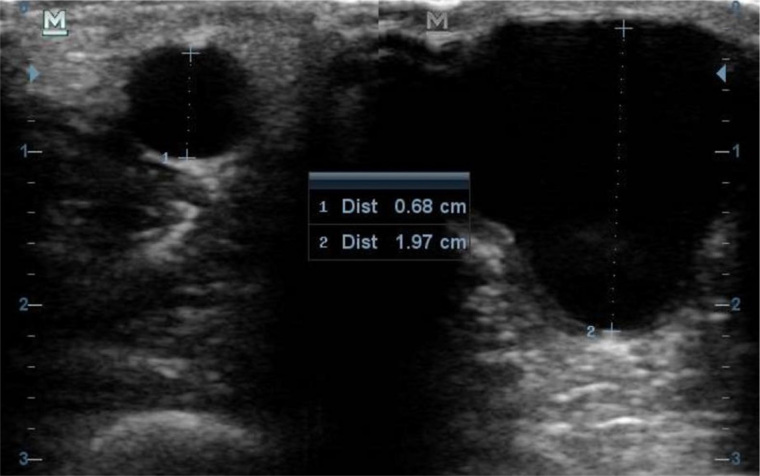

Results: Between 1 July and 31 August 2022, we recruited a total of 41 participants, of whom 56.1% were males. The mean age of the participants was 48.39 years. Radiocephalic (76%) and brachiocephalic (24%) arteriovenous fistulas were the only types present. The mean flow volume in the arteriovenous fistulas was 680.47 (365.98) ml/min, with 34.1% of the fistulas having a low flow volume. Also, 56.1% of the arteriovenous fistulas were stenosed, with the main site of stenosis being the juxta-anastomotic segment of the efferent vein. Aneurysms (53.7%), reverse flow (51.2%), venous luminal flaps (22%), and thrombus (17.1%) were the most common complications identified in the study population, with 78.05% of the arteriovenous fistulas having at least one complication. Factors associated with arteriovenous fistula stenosis included the patient body mass index and the radiocephalic fistula type. Diabetes, aneurysms, and luminal venous flaps were found to be associated with low flow volume.